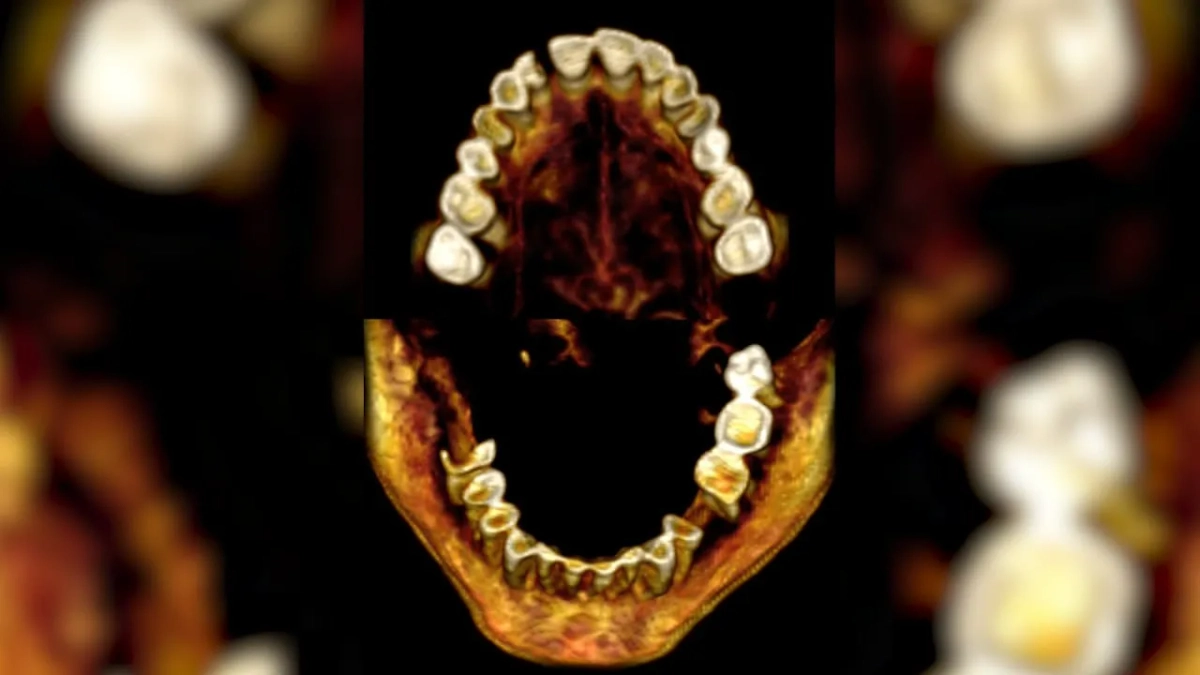

Зубы "кричащей" мумии, найденной в Египте. Фото © Frontiers in Medicine

Например, ранее считалось, что бальзамирование было выполнено некачественно. Однако последние изыскания показали, что всё сделали по высшему разряду и с применением дорогостоящих, даже дефицитных материалов. Инфракрасное излучение выявило, что женщина страдала артритом и проблемами с зубами: несколько она потеряла при жизни, а другие выдернули прямо перед кончиной.

И именно удаление зуба могло стать причиной шока или сердечного приступа, и мгновенного трупного спазма: мышцы закоченели, намертво застыв в одном положении.